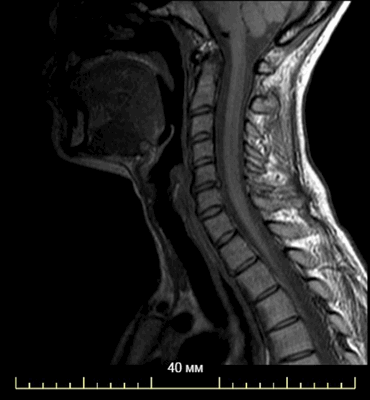

МР-снимок области шеи

Магнитно-резонансное сканирование - безопасный и безболезненный метод. Но процедура имеет некоторые противопоказания. Из-за конструктивных особенностей оборудования МРТ на томографе закрытого типа не выполняют людям с массой тела больше 120 кг. Аппарат не рассчитан на большой вес.

Киста шеи (щитоязычного протока) представлена на двух МР-снимках в разных режимах, имеет гиперинтенсивное содержимое на Т2 ВИ, четкий контур

Сканирование не требует подготовки. Разрешается пить и употреблять пищу. Но переедать не стоит, нахождение в замкнутом пространстве аппарата иногда провоцирует тошноту и рвоту. Стоит отдать предпочтение легкому перекусу, особенно при выполнении томографии с контрастом. Прием пищи позволит уменьшить признаки активности вегетативной нервной системы (тошноту, металлический привкус во рту и т.д.).